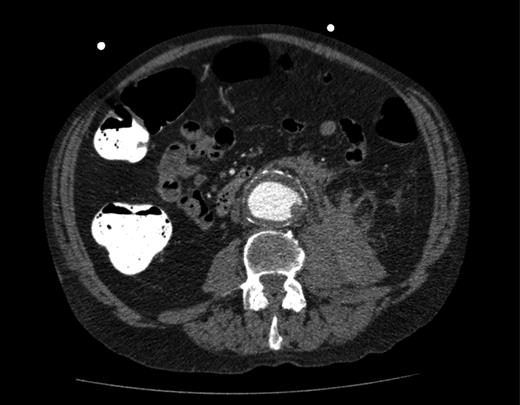

A computed tomography (CT) of the abdomen and pelvis was performed. This showed a grossly distended urinary bladder and compression of the sigmoid colon against the sacral promontory causing bowel obstruction (Figs 1 and 2, respectively) as well as a 4.9 cm abdominal aortic aneurysm without any signs of a rupture (Fig. 3). The plan was to consult our vascular colleagues regarding management of the AAA once the obstruction had settled.

Abdominal aortic aneurysm with some wall standing thrombus but without any signs of rupture.